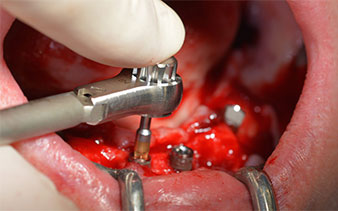

Изходът на долночелюстния нерв е първоначално идентифициран като ограничена анатомична структура и, след това, кортикалната кост на гребена е загладена с прав наконечник и голям борер с розовиден профил (Фиг. 4).

Хирургичният протокол за избраните импланти (SKY, bredent medical) изисква обороти от 1,200 rpm за пилотно пробиване с борера (Фиг. 7 - 9).

Това кореспондира със следващата зададена програма на Implantmed. Тук виждаме обратния наконечник на W&H под наклон от 45° ъгъл мезиокаодално в областта на 45, с цел да се предпази менталният нерв. Изходът на менталния нерв е използван като анатомична препратка за всички пробивания в тази зона. Следващите отвори са пробити при намалени обороти от 300 rpm (Фиг. 10 и 11).